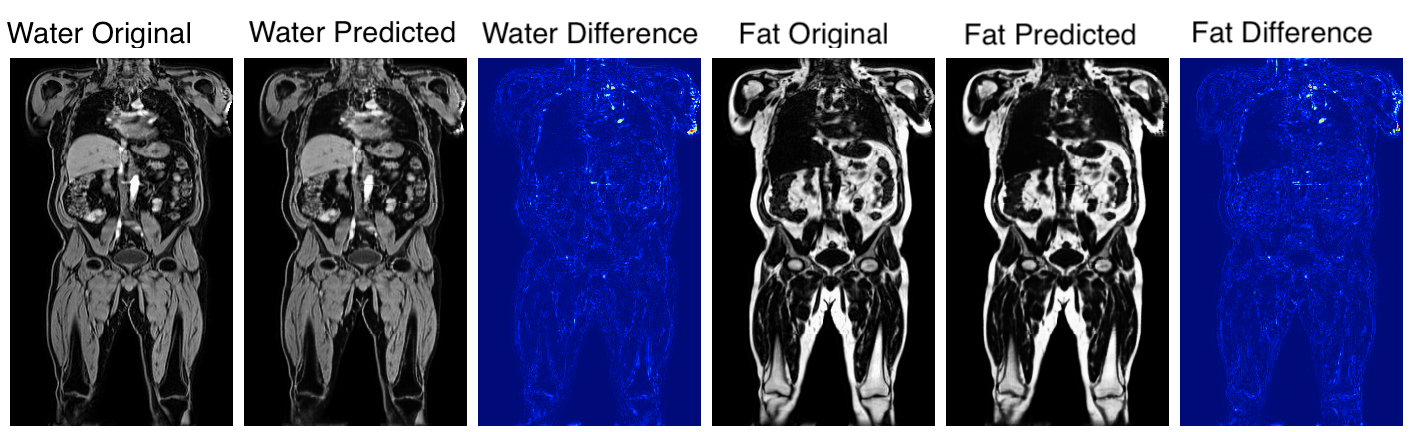

Fig. 3 shows the ground-truth data, predictions and their absolute difference for the fat and water channels of a participant in the testing set. Model predictions and the original data from the scanner for participants affected by various fat-water swaps are provided in Fig. 4. The examples were selected to illustrate the performance of our model in a variety of scenarios: data that are not affected by major swaps, data affected by swaps that cover an entire series in the acquisition (Fig. 4 a, c), as well as data displaying complex partial (Fig. 4 b, d, e) and/or boundary swaps (Fig. 4 f, g). The absolute difference images in columns 3 and 6 of Fig. 4 highlight where the original data have been affected by a fat-water swap in the scanner reconstruction but the model correctly predicted the fat and water channels. Fig. 5 provides examples of 3D segmentations using data that suffered from fat-water swaps (top row) and the segmentation when using our model predictions (bottom row) for the following organs and tissue (from left to right): abdominal subcutaneous adipose tissue, left kidney, spleen, and left/right iliopsoas muscles (red and green, respectively). The predictions shown in Figs. 3 and 4, as well as the underlying volumes used for the 3D segmentations in Fig. 5, are outputs of the final dual-input model, which performed the best across all of our experiments.

We successfully separated fat and water channels for 3D Dixon MRI in our three experiments, where the best model utilises both the in-phase and out-of-phase data as input with L1 loss. We have shown that our method correctly separates and channels and is able to overcome a wide variety of fat-water swaps, including those explicitly excluded from the training data (e.g., swaps that completely cover one of the series acquired, cover half the series in the legs, top-of-the-liver swaps). However, minor fat-water swaps located at the boundary of the field of view or only involving the arms were included in the training data as they occur infrequently and at random anatomical locations. We hypothesise that the infrequency and randomness of these types of swaps in the training data means that the model ignores them when optimising the generator. In Fig. 4, particularly rows e-g, it appears that the model is able to ignore and minimise the effect of the those swaps even though they were almost certainly present in the training data.